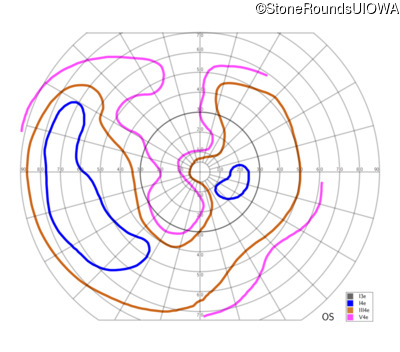

The clinical features supporting the diagnosis of Bardet Biedl syndrome in this patient include: bone-spicule-like pigmentation, narrowed arterioles and macular atrophy on ophthalmoscopy; photoreceptor loss on OCT; ulnar polydactyly, obesity, abnormal cognition, hypertension; and, normally sighted parents.